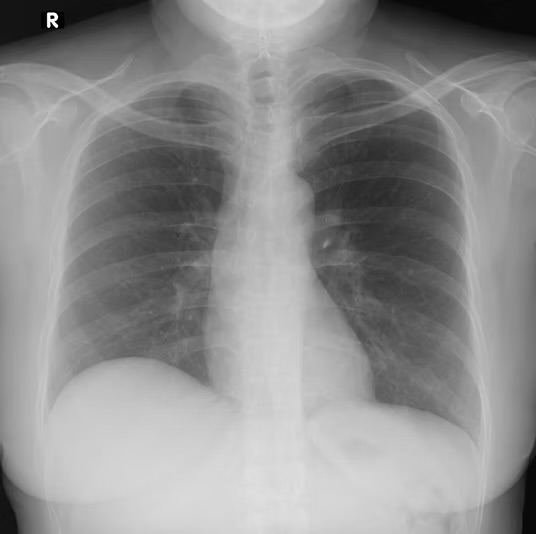

Edema y derrames

Los trastornos que afectan la función cardiovascular, renal o hepática suelen manifestarse con la acumulación anormal de líquido en los tejidos, fenómeno conocido como edema, o en las cavidades corporales,…